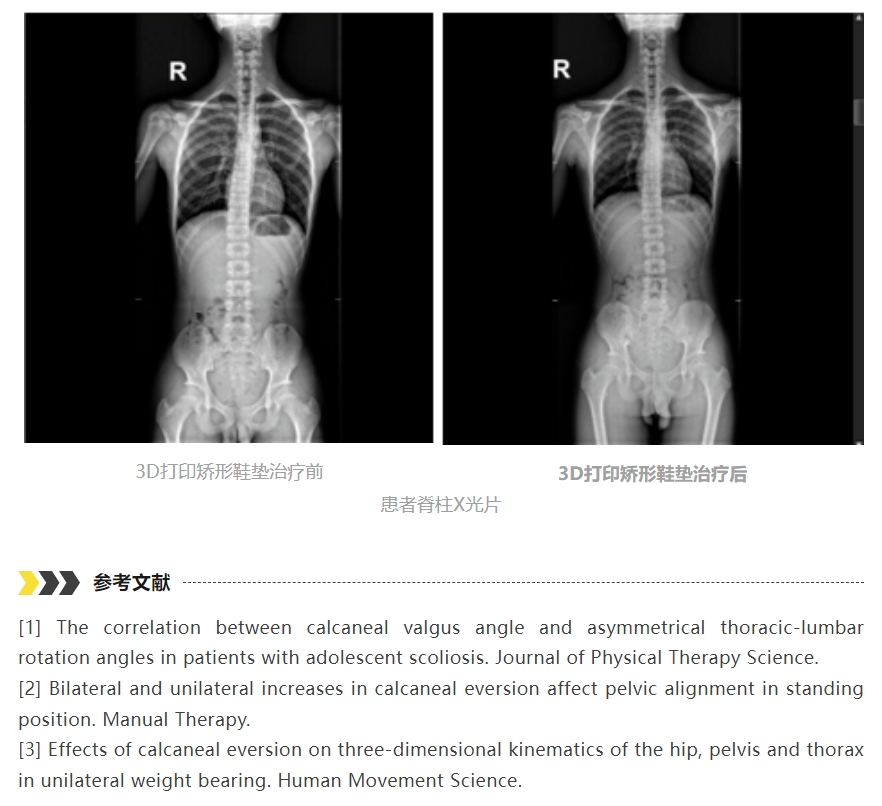

轻度代偿性脊柱侧凸可以通过3D打印矫形鞋垫矫正